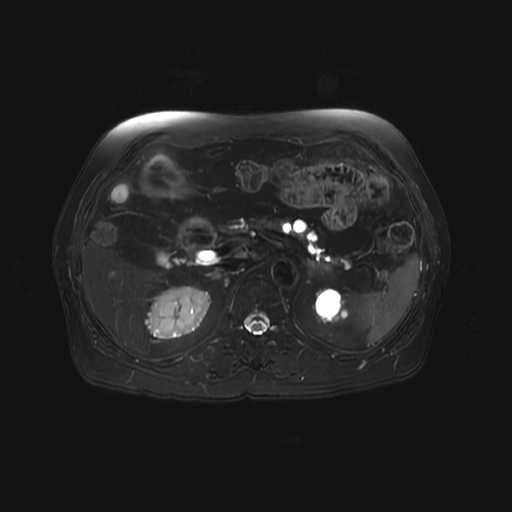

腹部

肝血管腫

膵管内乳頭粘液性腫瘍(IPMN)